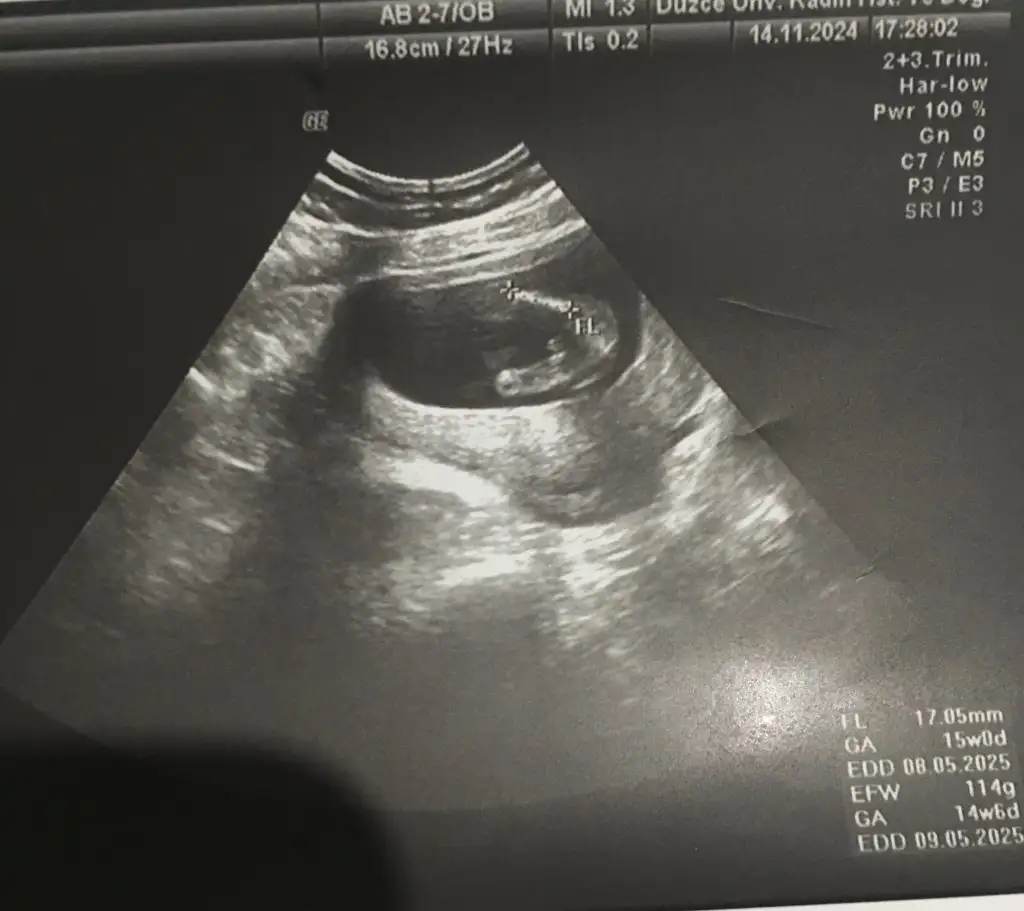

15. Hafta da erkek dendi 16 hafta da kız dendi ikisi de aynı doktor bakalım bir hafta sonra tekrar gidicem ne dicekler 🫣 15. Haftada ki ultrasonu da ekledim kesin konuşunca bizde ailelerimize erkek olduğunu küçük hediye ile söylemiştik bakalım nasip ne olucak 😂